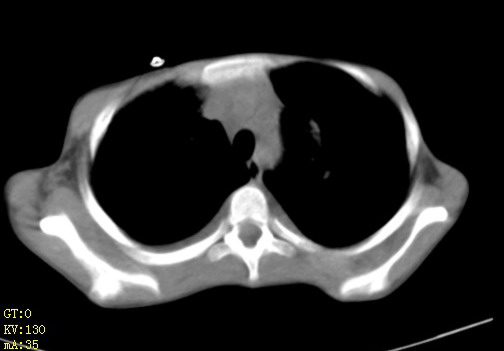

女,12岁,气促、咳嗽2天,3个月前查胸片示:两肺感染,急诊入院查ct,血常规等未检查。

先心(室缺?)、左室大,心功能不全;肺部感染

心衰 肺水肿

左肺上叶改变考虑继发性肺结核,余双肺重症肺炎不排除h1n1。双侧胸腔少量积液。

两肺感染,双侧少量胸腔积液;肺淤血及心脏改变,考虑心功能不全改变。学习了,望能反馈随访结果。

1、左心房、左心室增大,考虑左心衰, 2、肺水肿合并感染 3、双侧胸腔积液

双肺中下野不规则片絮状阴影,中外带明显,双侧胸腔少量积液,心影增大,心腔密度减低,隆突下及左侧气管旁见钙化淋巴结影,考虑双肺感染、心衰;建议结合临床除外h1n1并急性心衰,先心不能排除。

两肺多发片絮状模糊影,以下肺外带居多,内见支气管气像,纵膈窗未减影,两侧胸腔积液,心影增大,结合心超,支持重症肺炎,非常时期,甲型h1n1流感不排除。